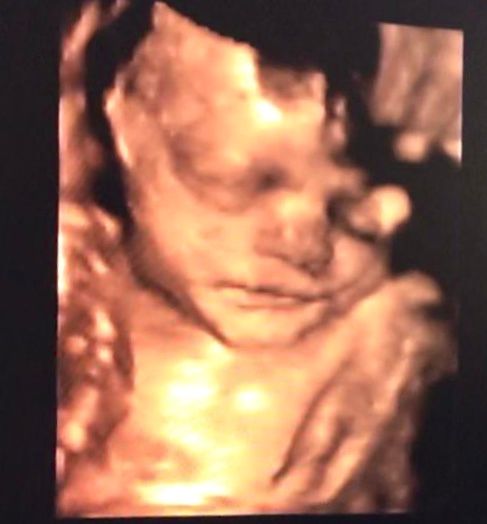

Che spettacolo!!eco in 3D

Effettivamente i risultati sono inimmaginabili sino a poco tempo fa